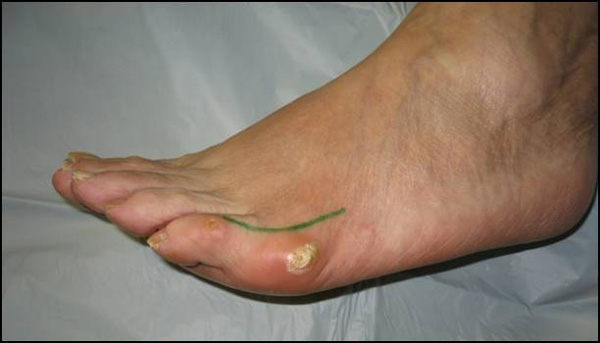

Schmerzen lateral, manchmal auch plantar, selten dorsal am Metatarsale V Köpfchen mit Schwielenbildung, akuter oder chronischer Bursitis.

Abb. 1a, b, c: Klinisches Bild eines Schneiderballens von dorsal, schräg und lateral.

Zum Lesen der Bildbeschreibung und zur Vollansicht bitte die Bilder anklicken.